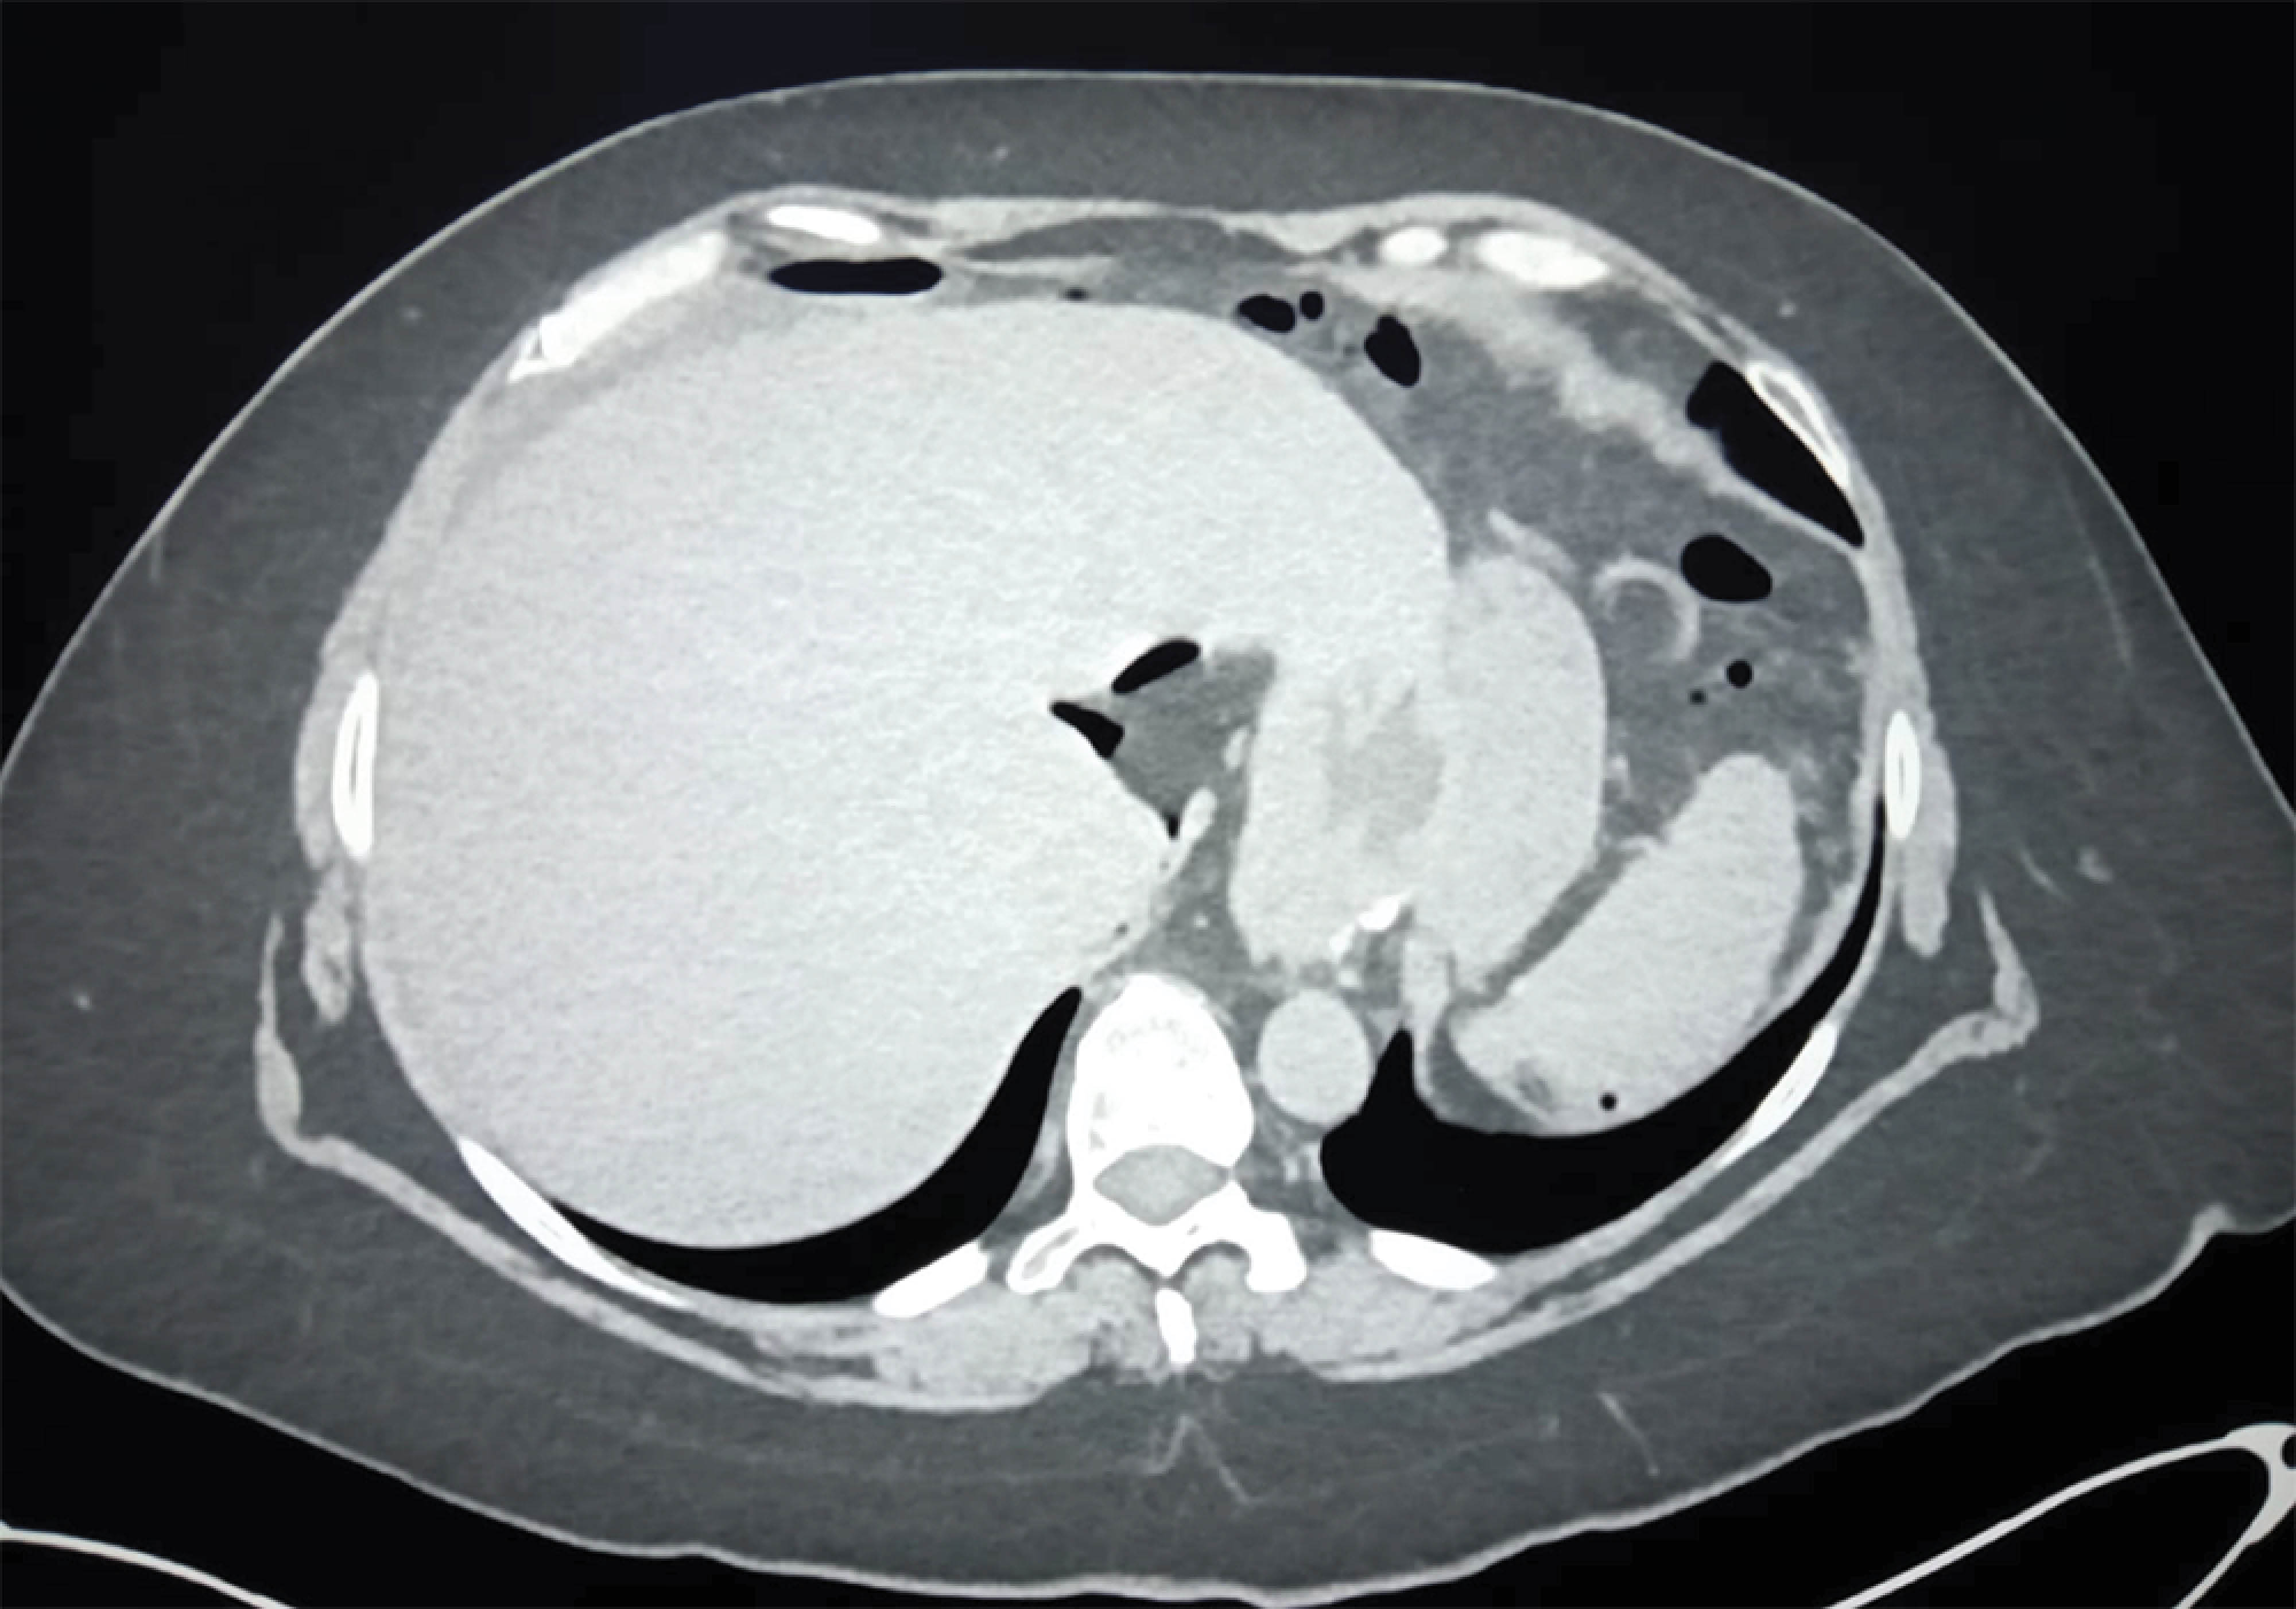

Management of late perforation of non-marginal jejunal ulcer in Roux-en-Y bypass patient

Peptic ulcer formation, while common in the stomach and duodenum, are rarely seen in the jejunum. Margin ulcer formation is the most frequent cause of jejunal perforation in patients with Roux-en-Y gastric bypass (RYGB). Non marginal jejunal ulcer perforation is an extremely rare condition. We present a case of a non-marginal late jejunal ulcer perforation in a patient with RYGB.

Figure 2